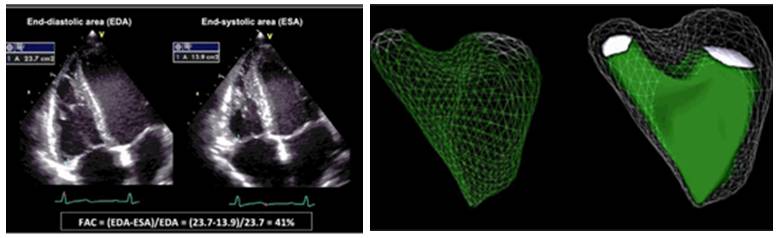

RV整体收缩功能:

FAC(右室面积变化分数) 三维RVEF

2015 ASE成人心腔定量测量指南